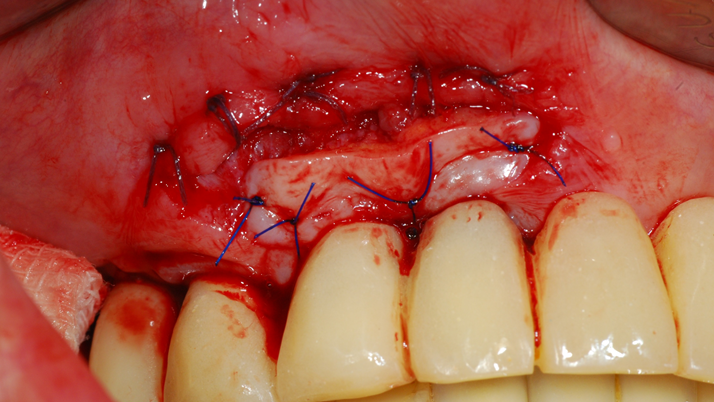

“Achieving a clean surface is the key to treating peri-implantitis!Using a titanium or NiTi brush for the decontamination process along with proper GBR can successfully restore the peri-implant environment. ”

Clinical case: Peri-implantitis treatment case using titanium or NiTi brush

- Courtesy of Dr. Dae-Hee Lee, South Korea -

Dr. Dae-Hee Lee,Maxillary Anterior,Peri-implantitis,Bone regeneration,Aesthetic zone,#21,#22,GBR,Titanium Brush Set